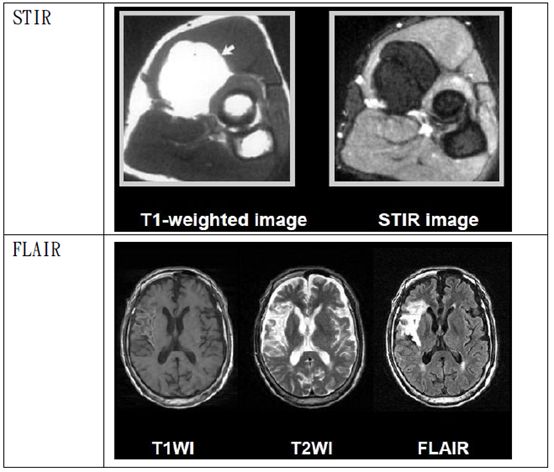

STIR Short TI inversion Recovery(TI反轉回復):

利用RF加在X軸,使磁矩在Z軸直接反轉,並等待組織成份進行recovery,通過“null point”之後才開始造影。例如:想抑制脂肪,就等脂肪通過null point再開始造影。然而在90°RF 脈衝之前先給予180°RF脈衝,這段時間稱之TI(inversion time)。脂肪屬於短TI,適當設定TI,即可抑制脂肪訊號,因此在影像上會是暗訊號。同理當抑制對象是水時,此方式稱“FLAIRfluid attenuated inversion recovery(流體稀釋反轉回復)

5d1aed48f0d05.jpg#s-554,304

5d1aed5011280.jpg#s-554,270

5d1aed5496e46.jpg#s-554,261

5d1aed598cfe7.jpg#s-554,472